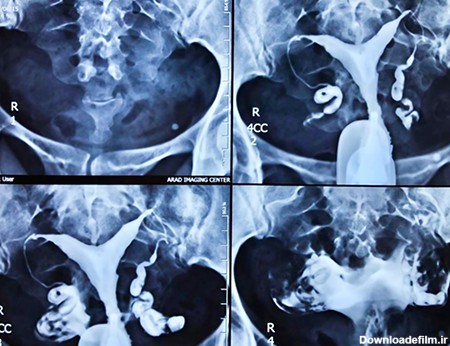

هیستروسالپنگوگرافی که به اختصار HSG گفته می شود در واقع همان تصویر برداری رنگی از داخل رحم و لوله رحم با استفاده از اشعه ایکس است....

عکس رنگی رحم چیست؟ یک آزمایش اشعه ایکس که برای بررسی رحم و لوله های فالوپ و ناحیه اطراف آنها نگاه می کند و برای بررسی مشکلات ناباروری ممکن است انجام شود.